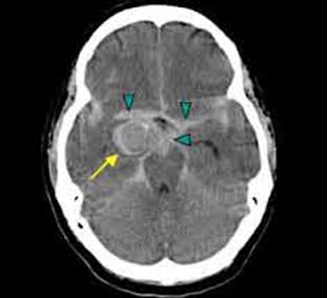

Anevrizmalar yırtıldığında sıklıkla subaraknoid (beyin ve beyin ince zarı arasına) kanama (SAK) gelişir. Damardan subaraknoid mesafeye yüksek basınç ile geçen kan burada birikerek beyne bası oluşturabilir, kanama beynin içine de olabilir; kan elemanları aynı zamanda daha düşük basınca sahip omurilik çevresine de ulaşabilir. Anevrizmadan olan kanama bazen sızma şeklinde de olabilir; bu durumda sızma noktasında küçük bir pıhtı oluşup kanamayı durdurabilir ve hasta yaşayabilir. Ancak pıhtının yol açtığı bu süreç tekrar kanama riskini önlemez; her ek kanamada yaşam daha fazla tehlikeye girer ve hayatta kalma ihtimali azalır. Kendiliğinden (spontane) gelişen SAK’ların çoğunun nedeni anevrizmalardır. Anevrizmanın yerinin, büyüklüğünün ve konfigürasyonunun tam olarak saptanması tedavisi ve dolayısı ile yeniden kanamanın önlenmesinde kritik bir noktadır. Bir kanama sonrası tekrar kanama ihtimali ilk 14 gün için yüzde 20 civarındadır. Beyin çevresine sızan kan damarlarda daralmaya (vazospazm) yol açabilir. Bu durum beyin dokusuna gelen kan akımında azalmaya ve dolayısıyla inmeye neden olabilir. Vazospazm genelde kanamadan 5-8 gün sonra gelişir. Tedavisi oldukçazordur, hastanın yaşamını tehlikeye sokabilir. Kanamış bir anevrizmadan sızan kan beyin-omurilik sıvısı (BOS) dolaşımını engelleyerek hidrosefali (beyinde aşırı sıvı birikmesi) dediğimiz tabloya eden olabilir. Bu durumda beyinde ventrikül dediğimiz boşluklarda aşırı sıvı birikerek kafa içi basıncının artmasına neden olabilir. Bu sıvı artışını engellemek için bu boşluklara dren yerleştirilerek biriken sıvı ve sızan kan dışarı alınmalıdır. Anevrizma kanaması beyin ödemi veya şişmesine de neden olabilir. Bu durum beyin fonksiyonlarını etkileyerek çok ciddi problemlere yol açar. Beyin dokusunun şişmesi ve basıncının artması beyin dokusuna zarar verir. Beyin ödemi kan damarlarında bası oluşturarak beyne kan gitmesini yavaşlatabilir.

Tanı Beyin Tomografisi ,Beyin Emarı vede Beyin anjiografisi ile yapılır. Tedavisi cerrahi olarak anevrizmanın kliplenmesi ya da uygun anevrizmalarda kasıktan girilerek anjio ile anevrizmanın tıkanması (coillenmesi) şeklindedir.